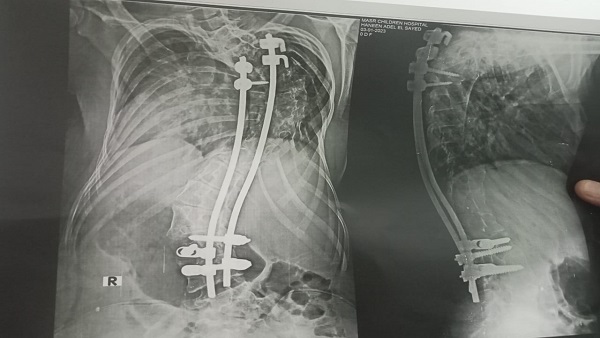

لم تتمكن حنين من الحصول على الدرجة الكاملة فى امتحانات نهاية العام بسبب إجرائها لعمليات جراحية فى العمود الفقرى وحصلت على 278 درجة من 280 حيث فقدت درجتين فقط فى مادة اللغة العربية.

حنين لم تكن تترك مذاكرتها حتى أثناء إجرائها للعمليات الجراحية التى أجرتها خلال العام الدراسى المنصرم، حيث أجرت ثلات جراحات خلال العام لكنها كانت تطلب الكتب الدراسية وتحرص على المذاكرة أثناء حجزها داخل المستشفى فى المرات الثلاث.

لم تكن الثلاث عمليات التى أجرتهم حنين هي أول الجراحات التى خضعت لها لكنها أجرت قبل ذلك 10 جراحات فى العمود الفقرى منذ ولادتها حتى أخبر الأطباء أسرتها بأنهم فعلوا ما فى إستطاعتهم ولم يعد هناك ما يستطيعون فعله، وأن الأمر بات يتطلب السفر لإجراء عملية جراحية بدولة ألمانيا.

وناشدت حنين وأسرتها المسئولين بوزارة الصحة إصدار قرار بسفرها للعلاج بالخارج حيث لا تمتلك الأسرة ما يمكنها من ذلك، حتى تواصل حنين تفوقها الدراسى والسير على قدميها مرة أخرى بشكل طبيعى.